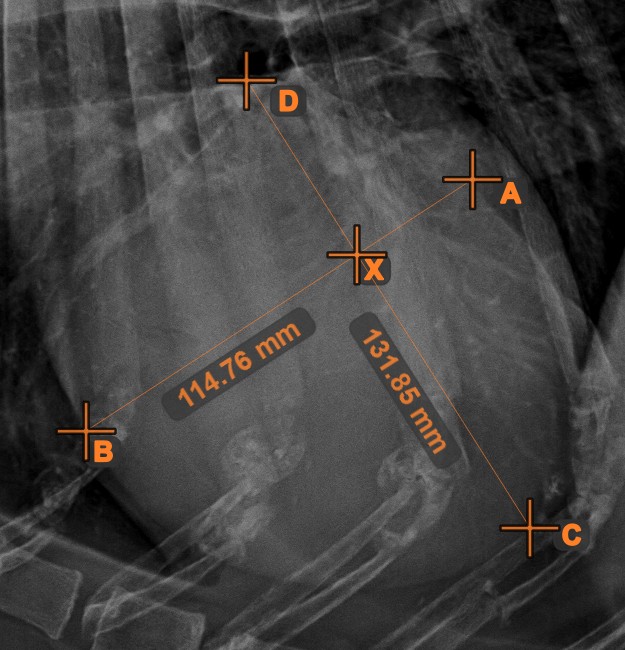

Line Intersection¶

Quickly and accurately locate and mark the intersection point between two existing lines by using the Line Intersection tool.

Select the tool from the left toolbar and assign it to one of the available mouse buttons. Select two lines that have already been drawn on the scene to complete the measurement. The intersection point of the line will be automatically calculated and marked on the scene. The intersection point of two lines will always be marked with the letter X.

Information

If two lines do not intersect directly, the intersection point of their extended projections on the scene will be marked.